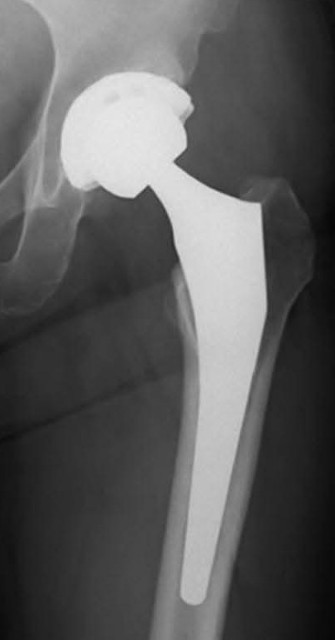

人工股関節

退院して一番困ること 人工股関節の寿命は約30年 経年劣化によるものか 平均的使用頻度によるものかわかりません 多分両方 ということは できるだけ負荷をかけない 即ち動かさないほうが良い がシモ 入院中はでたことを告げると 看護師が適切に処理してくれます が退院すると 自分でLavatoryに立たなくてはなりません すると股関節を動かします この二律背反が葛藤の種 立たないと 気色悪いことに 立つと人工股関節に負担が まぁそれも慣れました